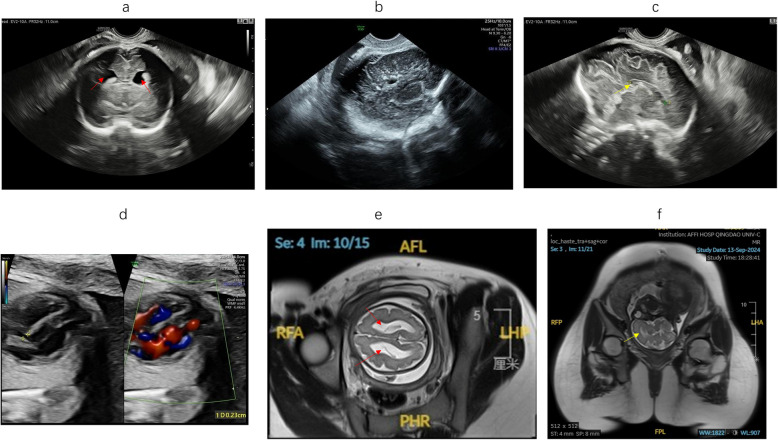

Background: Adams-Oliver syndrome (AOS) is a rare developmental disorder, and the DOCK6 gene is an identified AOS gene. This report highlights the prenatal diagnosis of AOS-2 by ultrasonography and genetic testing.

Methods: A growth-restricted fetus with bilateral ventriculomegaly, paraventricular calcifications, and ventricular septal defect underwent trio-whole-exome sequencing (trio-WES). Functional validation of the splice-altering variant was performed via minigene assays and protein structural modeling.